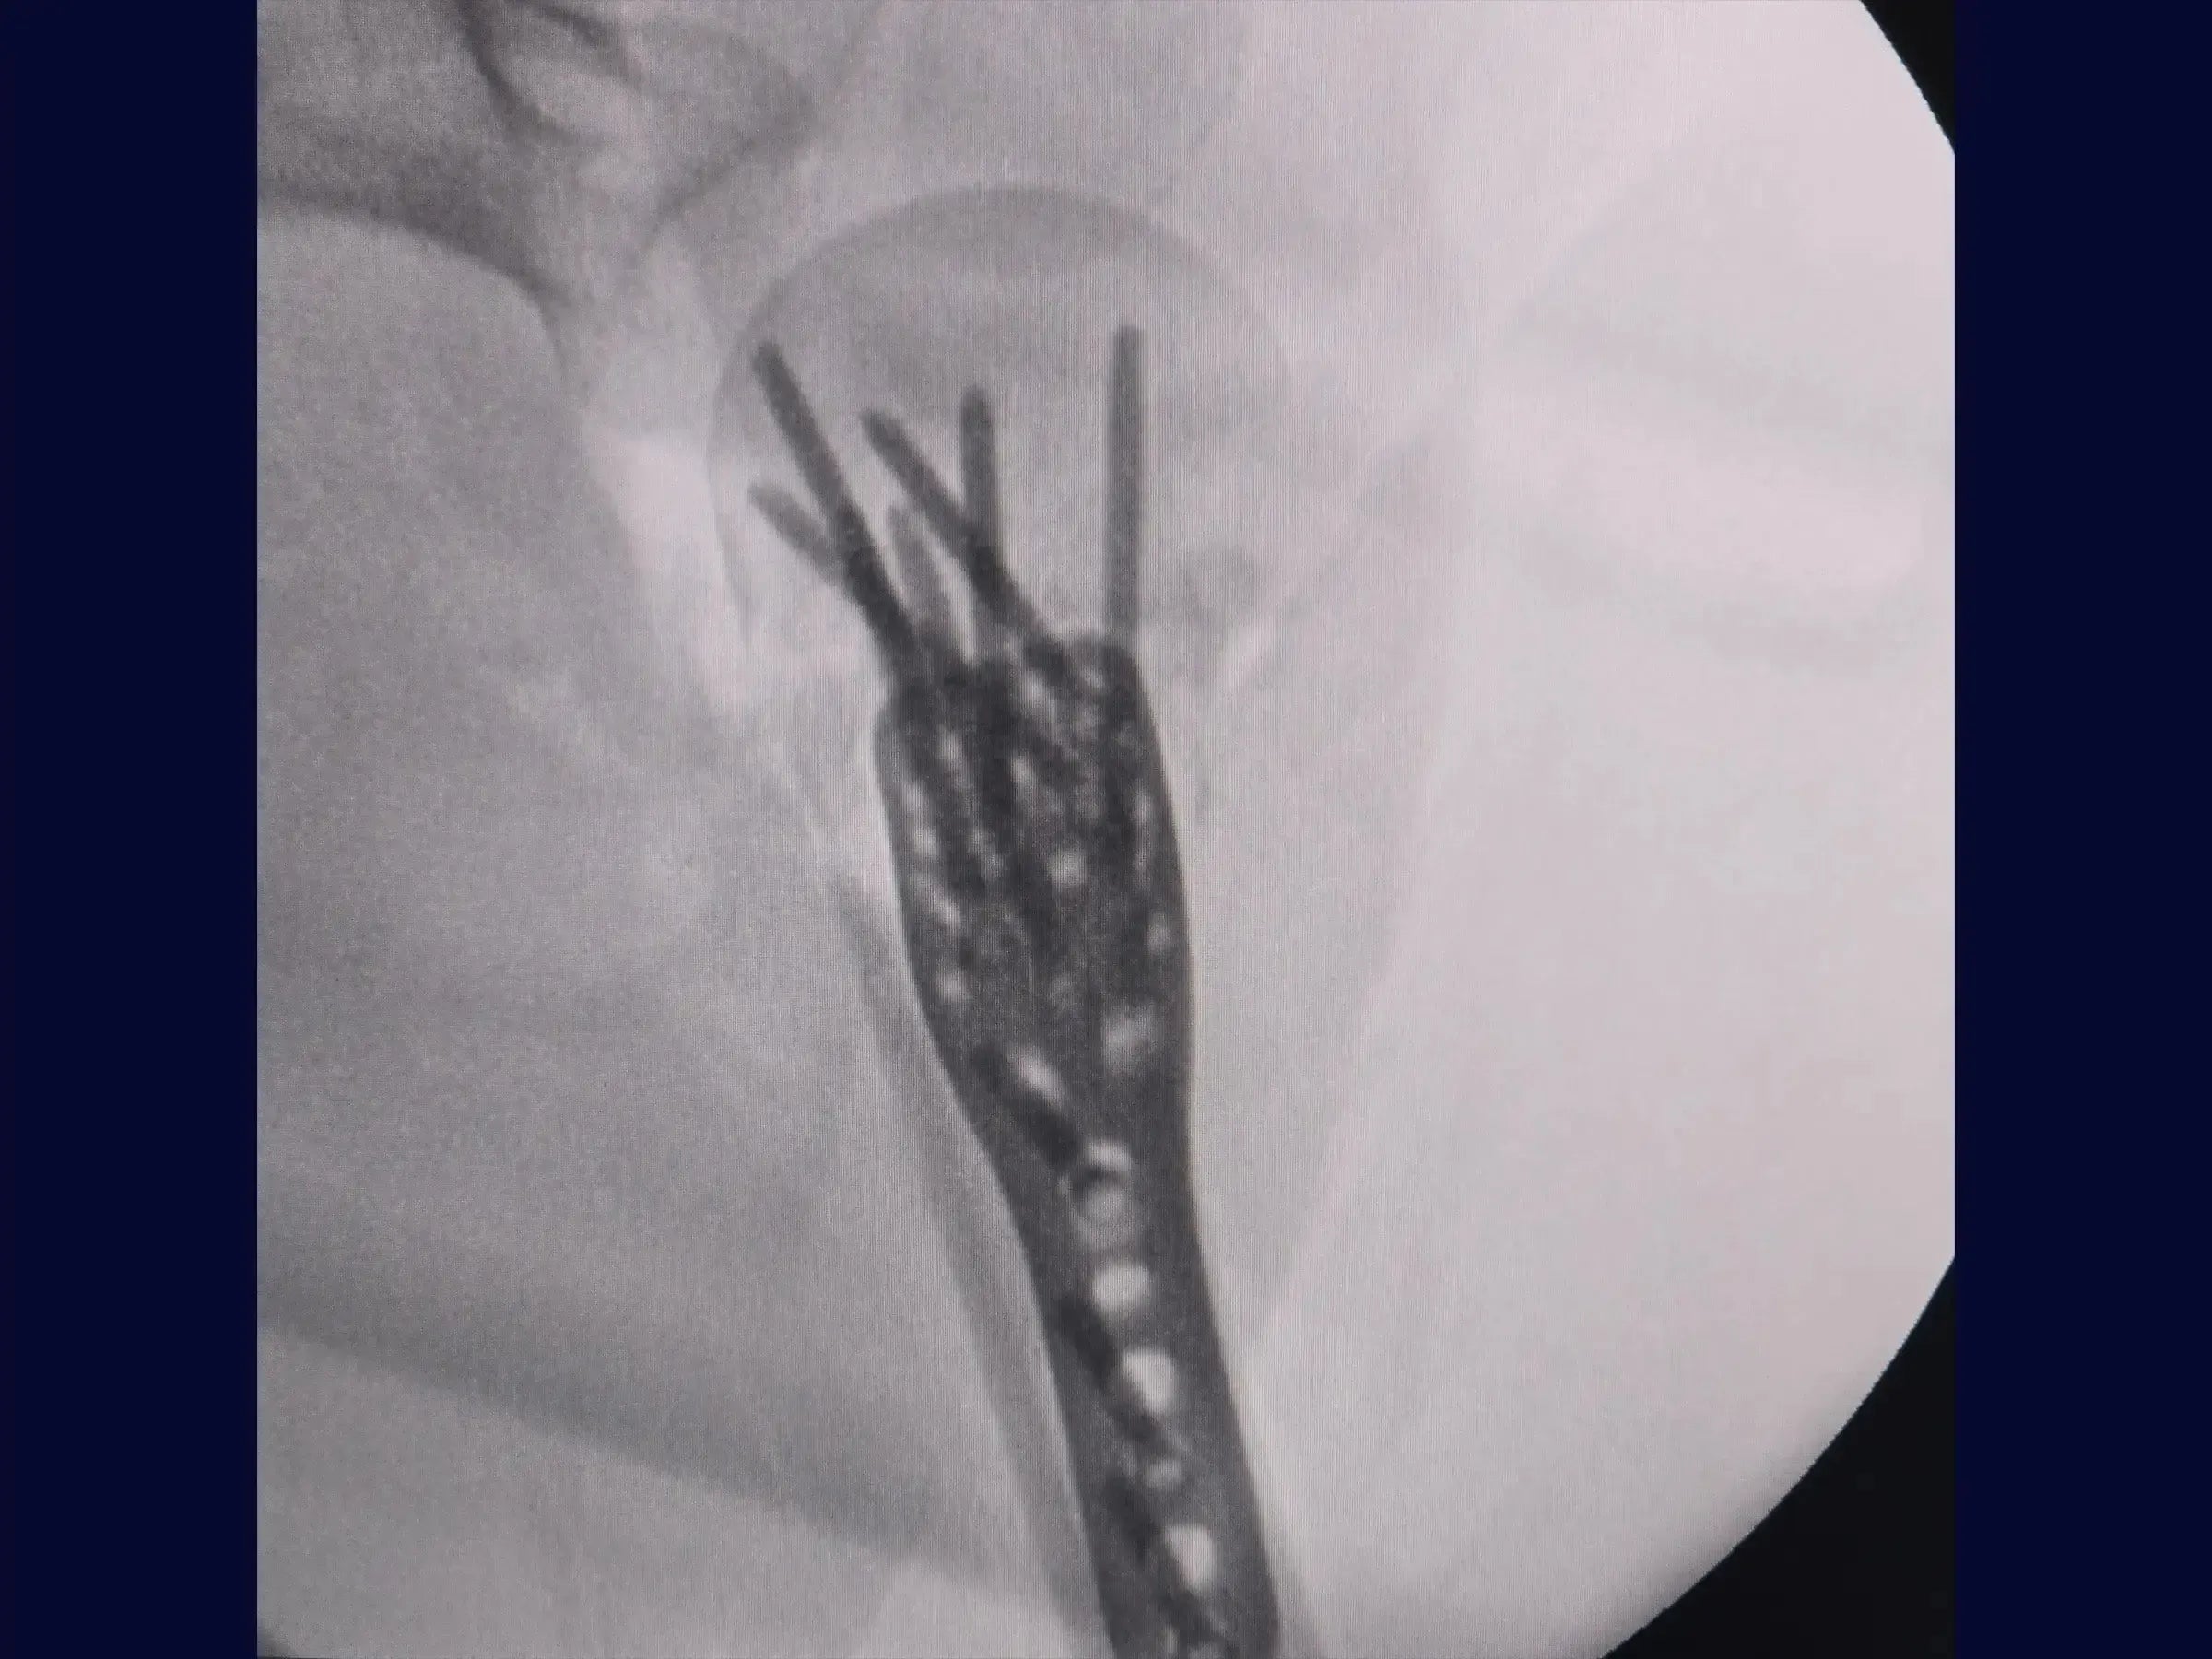

Reconstrução de Fratura Complexa em Quatro Partes do Úmero Proximal

Domine o tratamento de fraturas complexas do úmero proximal. Este treinamento oferece uma imersão técnica na reconstrução de fraturas em quatro partes, com ênfase na abordagem deltopeitoral e fixação com placa e amarrilhas, apresentada em vídeo 4K sob a perspectiva do cirurgião.

- Fixação com placa e amarrilhas.

- Posicionamento e Fixação da Placa: Princípios para posicionamento ideal da placa (1 cm lateral ao sulco bicipital) e inserção de parafusos, incluindo o parafuso dinâmico e parafusos no calcar para estabilidade e alinhamento.

- Tensionamento e Reforço das Amarrilhas: Metodologia para amarrilhas robustas com fios de alta resistência (FiberWire/FiberTape) nos tendões do manguito rotador, essenciais para a estabilidade rotacional e axial, com reavaliação e reaperto pós-valgização.